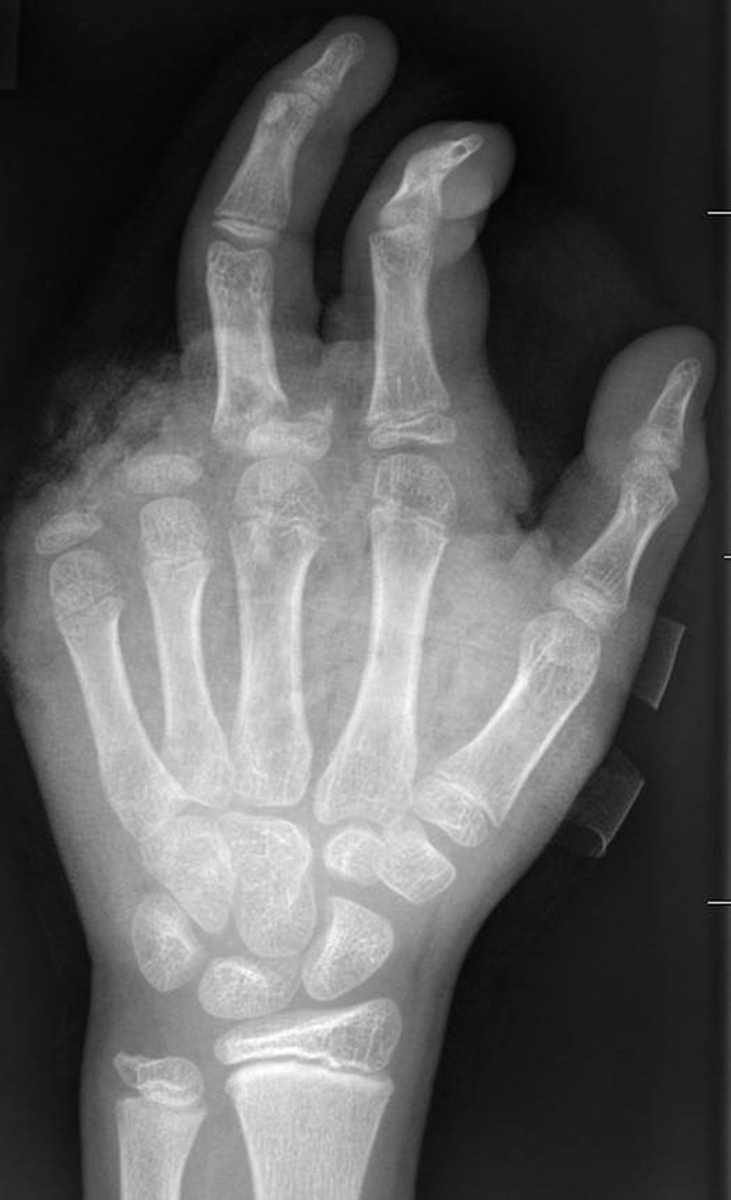

Abgetrennte Finger, durchtrennte Sehnen, Amputationen - die Handchirurgin Leila Harhaus-Wähner hat in der Silvesternacht schon vieles gesehen. Auch in diesem Jahr rechnet die Berliner Ärztin mit zahlreichen Böller-Verletzten. «Für Handchirurgen ist es klar, dass Silvester die arbeitsreichste Nacht sein kann.» Bis 24 Uhr passiere erstmal nicht so viel, ab 1 Uhr, 2 Uhr nachts kämen immer mehr Verletzte in die Notaufnahme und dann «sehr viele in sehr kurzer Zeit.»

In der Handchirurgie müssten an Silvester im Unfallkrankenhaus rund 20 bis 40 Menschen mit Böllerverletzungen operiert werden, sagt die Ärztin. Dieses Jahr werde sie mir vier weiteren Handchirurgen im Einsatz sein. Die häufigsten Verletzungen entstünden durch explodierende Böller in der Hand.

«Der überwiegende Teil der Verletzungen trägt tatsächlich lebenslange Folgen mit sich, weil die Sprengkraft dazu führt, dass eben nicht nur einzelne Strukturen verletzt sind, sondern immer mehrere. Und das heilt praktisch nie ganz folgenlos ab.» Zum Teil könnten Hände nicht mehr gerettet und müssten amputiert werden.